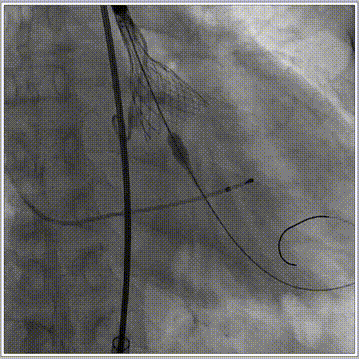

手术过程:

主动脉根部造影

球囊预扩

释放工作位评估

术后造影评估

跨瓣压差由术前38mmHg降低到5mmHg。